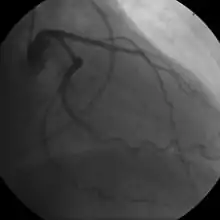

- Coronary angiography

In "stable" angina, chest pain with typical features occurring at predictable levels of exertion, various forms of cardiac stress tests may be used to induce both symptoms and detect changes by way of electrocardiography (using an ECG), echocardiography (using ultrasound of the heart) or scintigraphy (using uptake of radionuclide by the heart muscle). If part of the heart seems to receive an insufficient blood supply, coronary angiography may be used to identify stenosis of the coronary arteries and suitability for angioplasty or bypass surgery.[68]